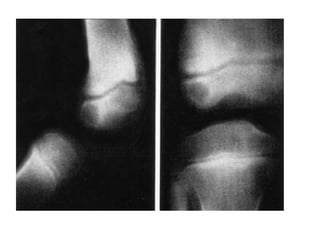

In the usual childhood manifestation, the infection begins in the metaphy-

bacterial growth (Fig. 7.1A); thence it may spread to involve a large part of the bone. The

subperiosteal abscess (Fig. 7.1B); later the abscess may burst into the soft tissues and may

Often the blood supply to a part of the bone is cut off by septic thrombosis of

the vessels (Fig. 7.1B). The ischaemic bone dies and eventually separates from

the surrounding living bone as a sequestrum (Fig. 7.1C). Meanwhile new bone

is laid down beneath the stripped-up periosteum, forming an investing layer

known as the involucrum (Fig. 7.1C). The epiphysial cartilage plate is a barrier to the spread of

infection, but if the affected metaphysis lies partly within a joint cavity the joint is liable to

become infected (acute pyogenic arthritis). Metaphyses that lie wholly or partly within a joint

cavity include the upper metaphysis of the humerus, all the metaphyses at the elbow, and

the upper and lower metaphyses of the femur (Fig. 7.2). Even when the joint is not infected it